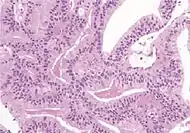

Ductal adenocarcinoma 3% to 12.7%[8][notes 1]

• Large glands and papillary formations, lined by tall columnar cells, often pseudostratified[1]

• Papillary, cribriform, individual glands, or solid variants[1]

• Cytoplasm usually amphophilic[1]

• Nuclei are large and hyperchromatic, with prominent nucleoli[9]

• AMACR+ in 77% of cases[1]

• Usually negative for basal cells stains[1]